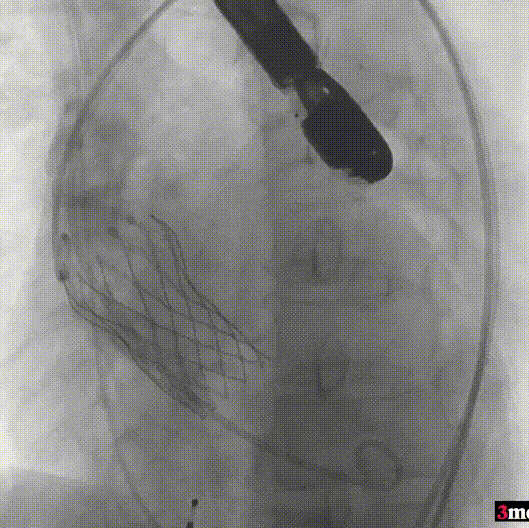

手术过程回顾:

患者全麻后,右侧股动脉建立主入路,主动脉根部造影显示主动脉瓣明显钙化。心室内轻微反流,主动脉及心脏情况整体较为稳定。直头导丝跨瓣后,在超硬导丝支撑下,瓣膜输送系统顺利跨瓣。在180次/分快速心室起搏下,确定降压至50mmHg后选择18mm球囊进行预扩张。在球囊扩张后,该患者血压未见升高,随即进行胸外按压,同时根据术前评估及球囊预扩情况,选取直径23mm瓣膜果断快速进行瓣膜定位并释放。瓣膜释放后患者心律和血压趋于平稳。

瓣膜释放至工作位

造影查看瓣膜形态

球囊后扩

最终造影

瓣膜释放后,超声提示患者存在一定的跨瓣压差和反流,通过球囊后扩,患者跨瓣压差即刻显著下降,反流量轻微。术后患者心功能持续得到改善,效果良好,此次手术取得圆满成功。